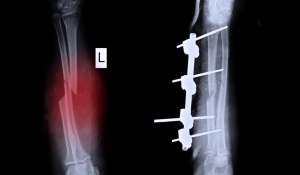

Остеосинтез переломів

Кожна травма має свої особливості та потребує індивідуального підходу. Тактика лікування та алгоритм дій при переломах кісток залежать від типу перелому, супутніх захворювань, способу життя та віку пацієнта, фізіологічних особливостей його організму.

Досвідчені ортопеди-травматологи МЦ «Медхауз» досконало володіють усіма методами оперативного втручання на опорно-руховому апараті. Одним з них є остеосинтез. Виняткова майстерність наших фахівців і досконале володіння технікою остеосинтезу будь-якої складності, допомогло зберегти повноцінне якість життя сотням пацієнтів зі складними переломами та іншими травмами.